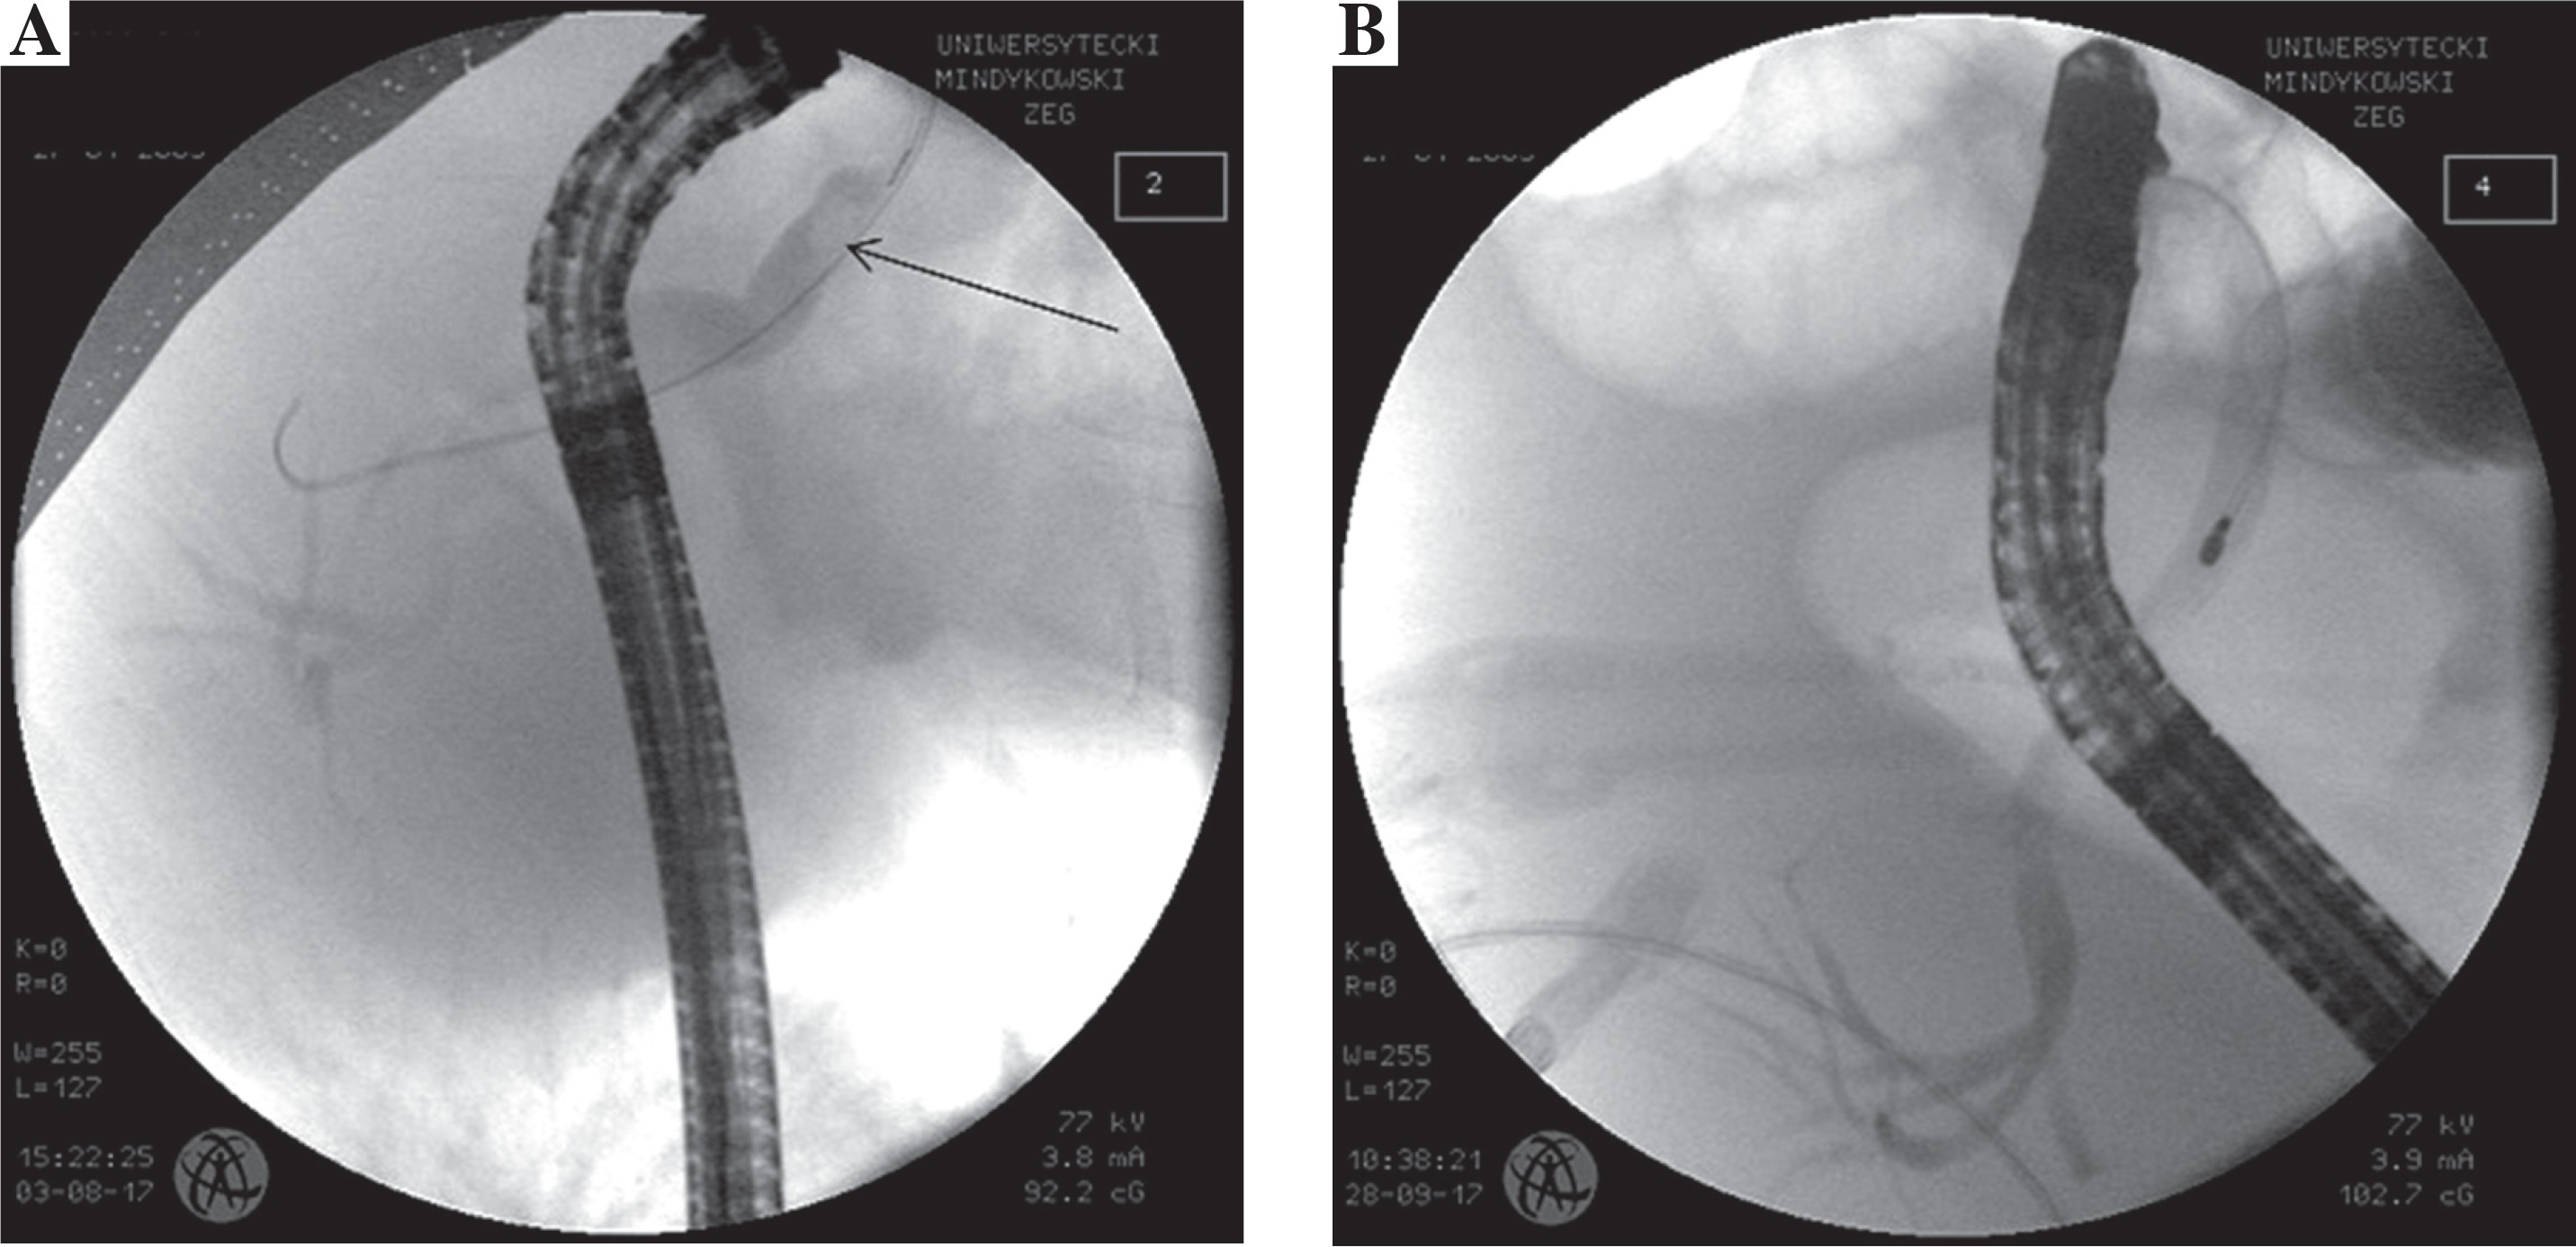

Two weeks later she was admitted to hospital with mild acute lower gastrointestinal bleeding. Stool samples were tested negative for rotavirus, adenovirus and norovirus, but positive for Campylobacter jejuni and Clostridium difficile. Blood CMV and EBV reactivation were also ruled out. The ileocolonoscopy revealed a 3-4 cm crater-like ulcer located 2-3 cm from the anal margin, which was covered by yellowish slough surrounded by reactive mucosa. Another ulcer was found at the recto-sigmoid junction (Fig. 3). Microscopically, lymphocytic and neutrophilic mucosa infiltrate that focally infiltrated crypt epithelium with mild crypt distortion and signs of regeneration were present in the entire colon. Based on histopathology, CMV infection and GVHD in the colon were excluded. The girl was treated with intravenous azithromycin and orally budesonide and mesalamine. A clinical and endoscopic improvement was noted at the second endoscopy performed four weeks later.

Fig. 3

Endoscopic picture showing deep 2 cm in diameter crater-like ulcer located at the recto-sigmoid junction covered by yellowish slough with inflamed surrounding mucosa (day +104)